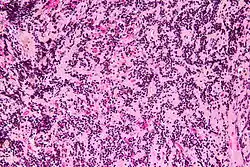

Micrograph of a pineocytoma. HPS stain.